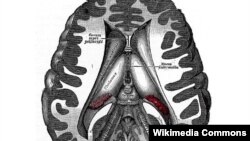

Австралійські учені зробили рішучий крок на шляху ранньої діагностики різних форм старечого послаблення розуму, божевілля (включно з хворобою Альцгеймера). Результати досліджень опубліковані в журналі Molecular Psychiatry.

Науковці, зокрема, знайшли можливість визначати ці процеси на ранній стадії завдяки аналізам крові. Так, наприклад, поява токсичних протеїнів у мозку спостерігається за багато років до виникнення симптомів хвороби Альцгеймера, коли ще не виникають неповоротні руйнівні пошкодження мозкових клітин.

Учені дійшли висновку, що виявлення попередніх симптомів заздалегідь дає ліпші шанси на отримання лікування до того, як буде вже пізно щось робити.

Ще одне дослідження уточнило, що знайдені протеїни дають можливість передбачити появу хвороби за 17 років до виникнення перших її симптомів.